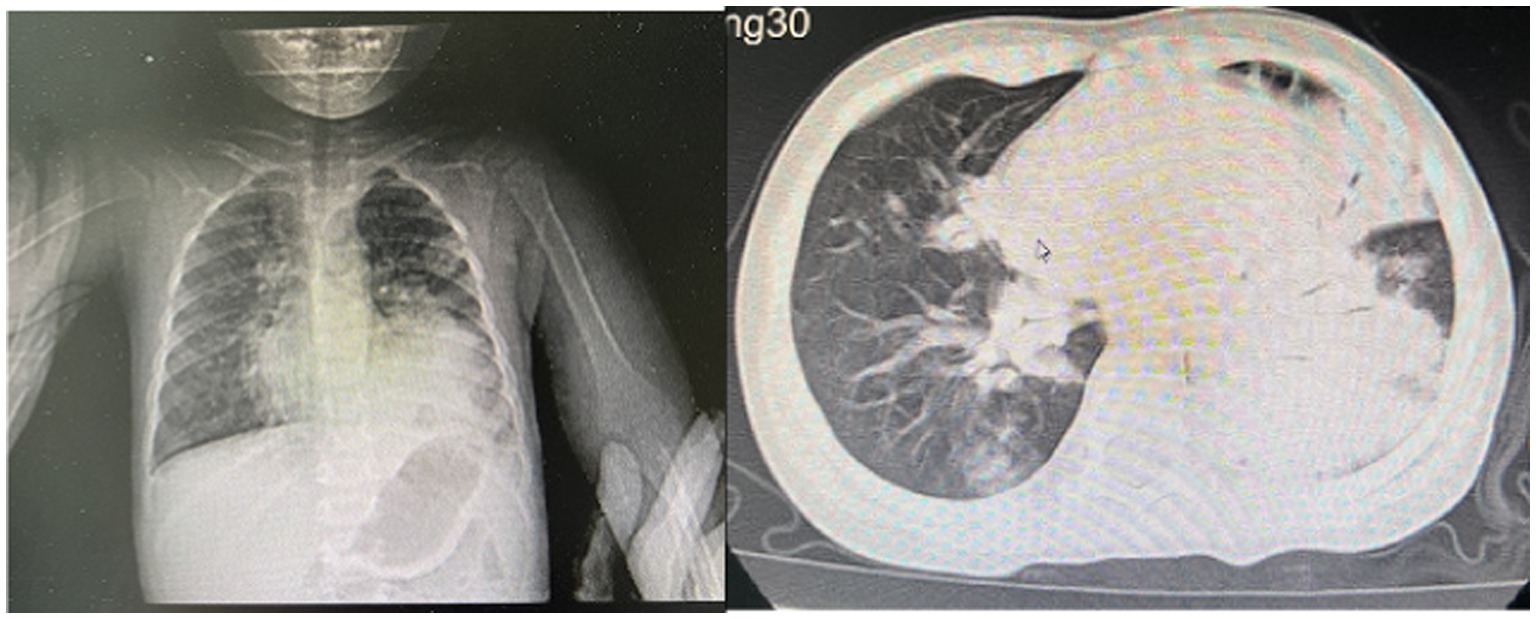

Post-treatment, the patient’s temperature normalized, with occasional cough but no dyspnea or respiratory distress. The patient was discharged. Follow-up chest CT on day 67 (Figure 4) showed reduced cavitary lesion size and number, with surrounding consolidations. By 9 months post-onset, further reduction in cavity size, consolidations, fibrous strands, and localized bronchiectasis was noted. By 17 months (Figure 5), only minimal residual cavitary lesions, consolidations, and localized bronchiectasis were observed, without further significant changes compared with the 9-month follow-up. The patient’s clinical Event, Diagnostic Findings, and key interventions are summarized in Table 2.

Figure 4

Chest CT scan on the 67th day of the illness.

Figure 5

Chest CT scan at the 17th month of the illness.